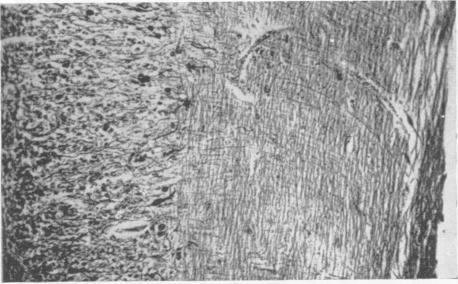

A benign tumour of the cerebellum; report on two cases of diffuse hypertrophy of the cerebellar cortex with a review of nine previously reported cases.

J Neurol Neurosurg Psychiatry. 1955 Aug;18(3):199-213. doi: 10.1136/jnnp.18.3.199.